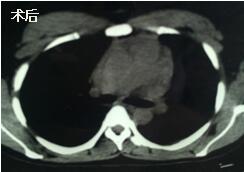

當(dāng)看到病人的CT等外院各項檢查時,我頭皮發(fā)麻,心頭發(fā)怵:巨大的腫塊占據(jù)著整個縱隔,壓迫心臟,與血管關(guān)系密切,初步考慮侵襲性胸腺瘤、胸腺癌或淋巴瘤等,合并腎功能不全,無法完整切除,手術(shù)風(fēng)險大,手術(shù)并不能提高病人長期生存率,換言之,小伙子等待的是生命的立即終結(jié)。

當(dāng)看到病人癥狀緩解,復(fù)查胸部CT幾近完美,我們那種自豪感油然而生。偶爾去治愈,常常去幫助,總是去安慰,我們深知,小伙子的人生之路并不長,只能深深祈禱他在我們的治療下能走得更遠(yuǎn)一些,能把剩下的日子走的更充實(shí)一些。而我們在能夠幫助人的時候,別一味地去安慰,永不言棄,是我們這一群胸外人堅貞的信念。